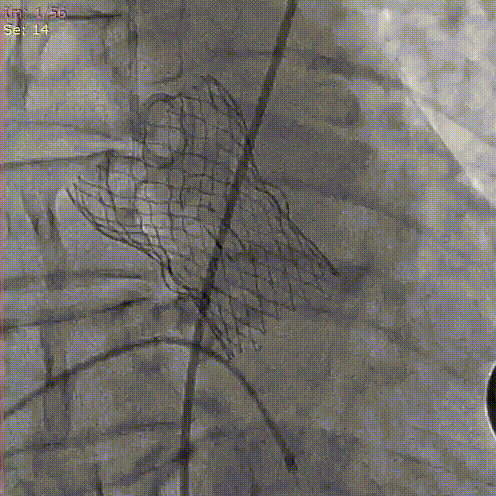

手术关键步骤

A.预扩张,并同时行主动脉造影

B. 冠脉保护:导丝、球囊、Guidezilla、位于LAD;Guiding回撤至升主动脉适当位置

C. 应用交界贴合技术调整人工瓣膜,标准位释放瓣膜并行释放后造影

D. 瓣膜释放后造影显示瓣膜位置良好

E.后扩张

F. 最终造影显示瓣膜位置良好冠脉开口血流正常,撤出冠脉保护